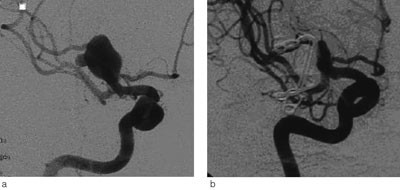

Universitetssykehuset er regionsykehus for vel 470 000 innbyggere i Helse Nord. Nevrokirurgisk avdeling har siden 1986 utført kirurgisk behandling av intrakraniale aneurismer (fig 1) (11). Endovaskulær behandling ble introdusert i 2000 (fig 2).

Vi behandlet 51 (63 %) av 81 rumperte aneurismer og 24 (75 %) av 32 ikke-rumperte aneurismer kirurgisk. Alle, unntatt to gigantaneurismer som ble pakket med gasbind og vevslim, ble lukket med klipsligatur. De øvrige 38 aneurismene (30 rumperte og åtte ikke-rumperte) ble behandlet endovaskulært med coiling. Blant pasienter som hadde hatt subaraknoidalblødning, var det ingen signifikant sammenheng mellom Hunt & Hess-grad eller Fisher-grad og valg av behandlingsmetode.

Behandlingsmetoden var avhengig av aneurismets lokalisasjon. Aneurismer utgående fra a. cerebri media ble vanligvis lukket med klipsligatur (43 av 46 tilfeller, 93 %), mens alle aneurismer i bakre kretsløp ble behandlet endovaskulært. For aneurismer utgående fra a. carotis interna og a. cerebri anterior var fordelingen av klipsligatur versus endovaskulær behandling henholdsvis 42 % versus 58 % og 58 % versus 42 %.

Prosedyrerelaterte komplikasjoner

74 (69 %) av 108 prosedyrer forløp uten nevrologiske komplikasjoner. Det oppstod forbigående eller varig hemiparese, afasi eller kognitiv svikt hos 34 pasienter (31 %). Forekomsten var 41 % etter kirurgisk behandling og 16 % etter endovaskulær behandling (p = 0,009, Fishers eksakte test). En pasient som hadde hatt subaraknoidalblødning med preoperativ Hunt & Hess-grad IV, fikk reblødning under operasjonen og døde to døgn senere på grunn av høyt intrakranialt trykk med herniering. Det var ellers ingen signifikant forskjell i forekomsten av prosedyrerelaterte komplikasjoner mellom pasienter behandlet for rumperte (31 %) og pasienter behandlet for ikke-rumperte aneurismer (28 %).